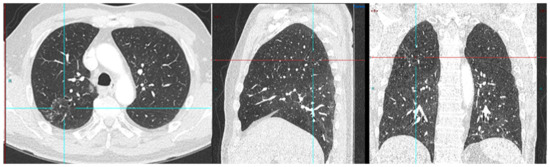

Figure 3.

Radical prostatectomy negative scan at PSA 3.5 ng/mL, indeterminate lymph node at PSA 6.5, rise of 3 ng/mL in 2 years RADS 3A—RP status. Consolidation in right upper lobe. Resolved on follow up CT after 2 months.